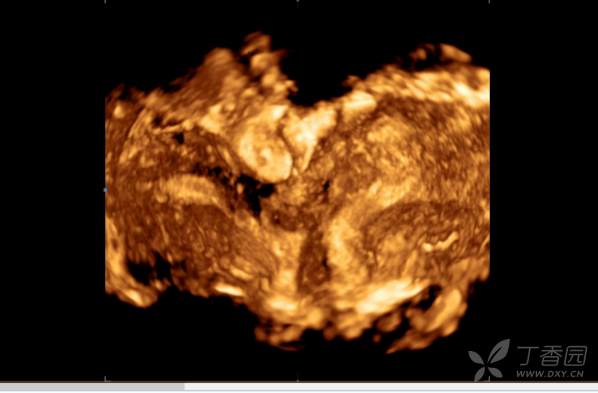

简要病史:此次患者来我院求医是因2020年12月右侧宫腔胚胎移植失败,生殖科考虑患者左侧宫腔条件比右侧宫腔要好,但多次宫腔镜未能探入左侧宫腔,B超提示左侧子宫内膜厚,回声不均(未见单),建议宫腔镜。阴道三维彩超:两个子宫大小分别为5.0×4.6×3.6cm(左侧 ),4.8×4.2×3.1cm(右侧 ),横切面宫底部为蝶状,宫体部横径增宽,可见两个宫腔内膜回声,左侧厚约1.0cm,回声不均匀,右侧厚约0.6cm,宫颈部呈哑铃状。复查彩超:双子宫,右侧宫腔内膜厚0.5cm,左侧宫腔内可见分离暗区,左侧子宫下段部分内膜中断,该处至宫颈外口长约4cm的范围内未见内膜回声。